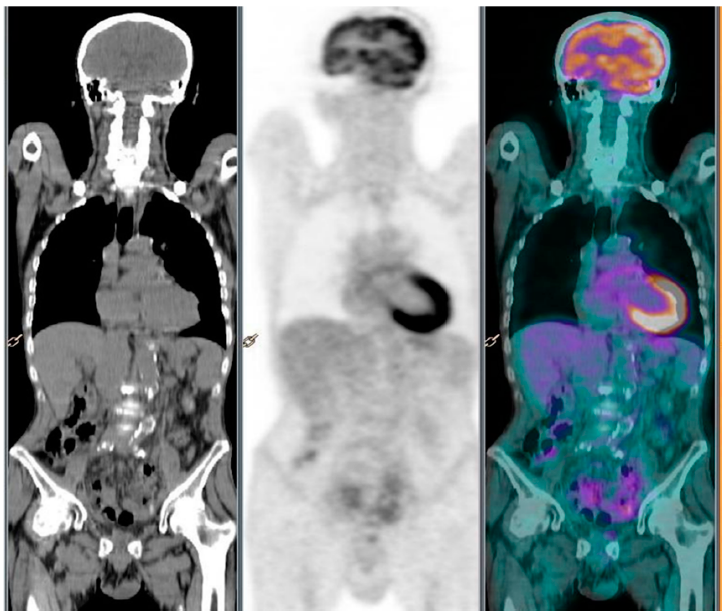

2. Case Report 1

3. Case Report 2